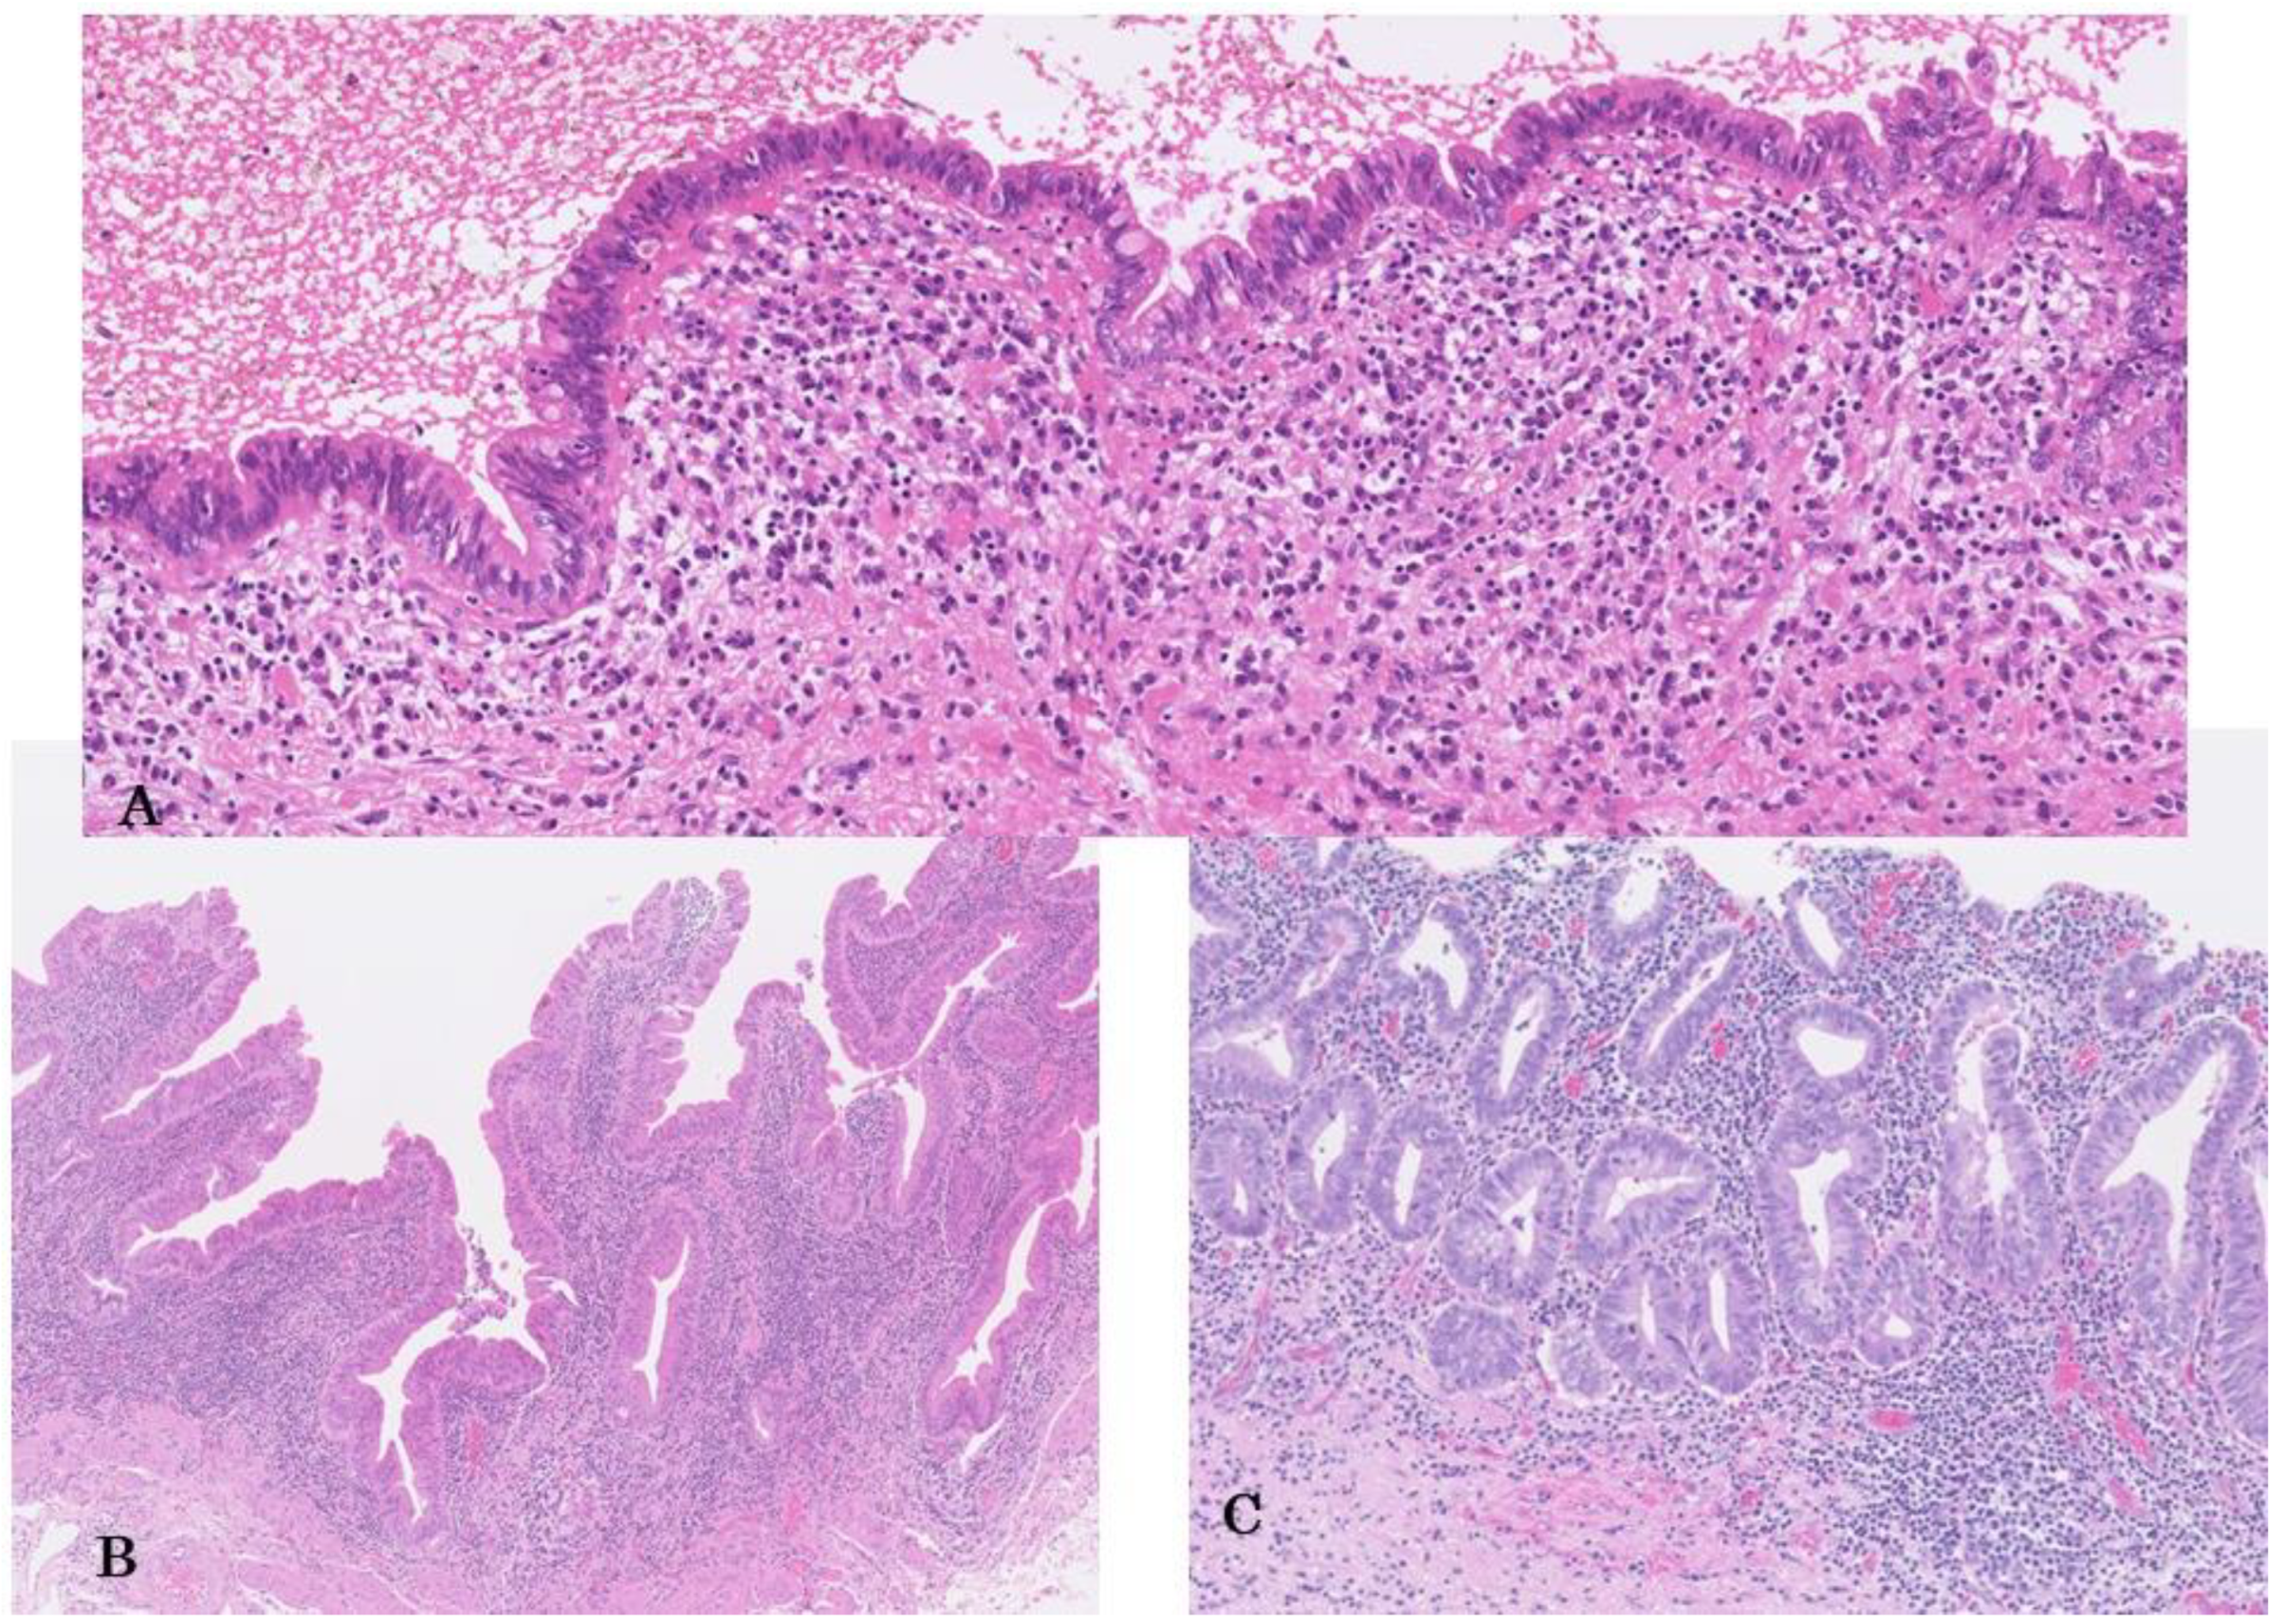

3.1.2. Gross and Microscopic Features

3.1.3. Grading

3.1.4. Four Subtypes